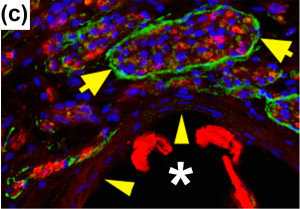

Figures A-D: Immunostained regenerating tissues after 6 weeks; (a and b) mid-conduit sections were stained for GLUT1 (green)/S100 (red)/DAPI (blue) in (a) NoMgSa and (b) MgSa animals (*cavity left by Mg, arrows delineate conduit material, bar=300μm). (c and d) Regenerating nerve mini-fascicles, indicated by arrows, run close to the Mg cavities, which are marked by * and arrowheads. The same staining was done on the section in (c), while the section in (d) was stained with ED1 (green)/NF200 (red)/DAPI (blue). Note GLUT1þ perineurium in (c) and thin layer of ED1+ macrophages above arrowheads in (d) (bar in c and d=50μm).

NoMgSa: saline filler only; MgSa: saline and Mg; GLUT1: glucose transporter 1; DAPI: 4’ 6-diamidino-2-phenylindole.2